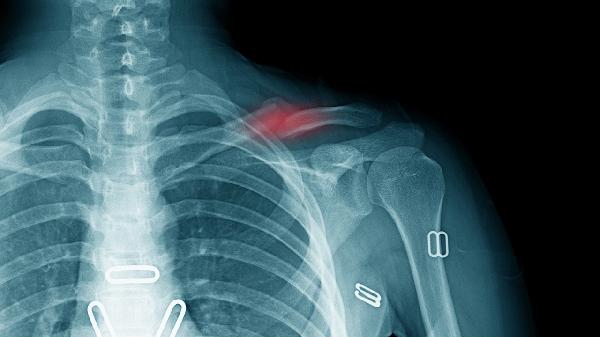

锁骨骨折错位多数情况下可以保守治疗。治疗方案选择主要取决于骨折类型、错位程度、患者年龄等因素,常见处理方式包括八字绷带固定、锁骨带固定、功能锻炼、定期复查及手术评估。

保守治疗期间每2周需影像学评估。若发现骨折端分离超过2厘米、持续疼痛或皮肤隆起,提示可能存在延迟愈合。儿童患者需特别关注生长板损伤风险,成人需警惕创伤性关节炎早期征象。

开放性骨折、严重粉碎性骨折或合并血管神经损伤需手术干预。钢板螺钉内固定可精确重建解剖结构,髓内钉适用于长斜形骨折。术后2周开始被动活动,6周后逐步负重训练。